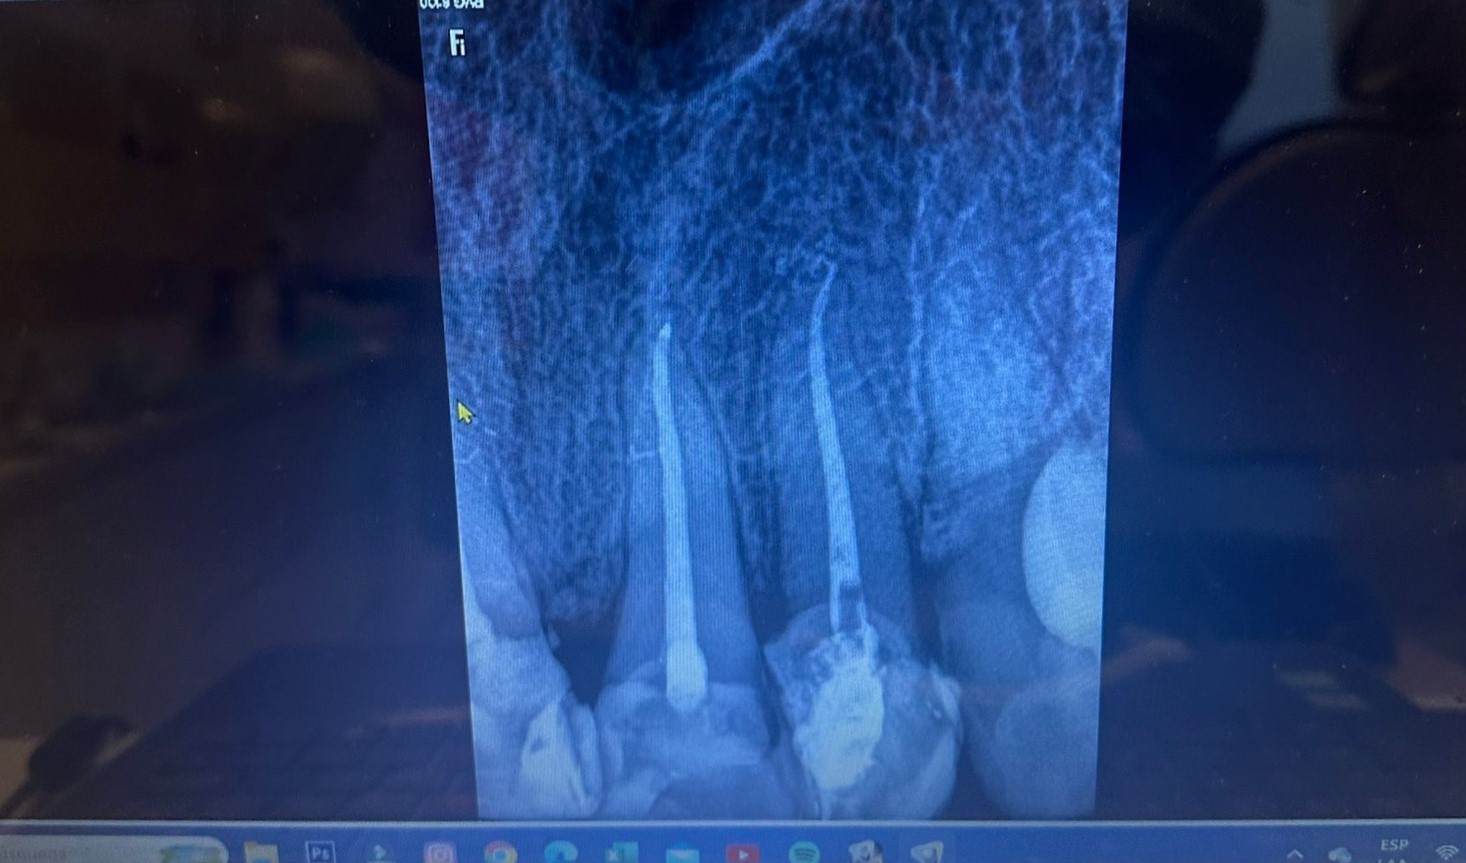

El tratamiento endodóntico es un procedimiento para tratar los conductos radiculares del diente, donde la mayoría de las veces debido a una reparación inoportuna de una lesión cariosa o lesiones traumáticas en el diente, se produce una infección del tejido del interior de los conductos radiculares.

Durante el procedimiento y después de completar cada paso del mismo, se toman radiografías para verificar y confirmar el resultado obtenido.

La radiografía es el método más rápido y confiable para verificar el éxito.

Hoy en día, en las radiografías panorámicas de rutina, se observan con mucha frecuencia conductos radiculares mal curados que en el pasado se trataban según el método clásico: el tratamiento manual de conductos. Teniendo en cuenta que en aquel entonces se disponía de materiales y técnicas para el tratamiento manual de conductos, una buena parte de los conductos permanecían sin tratar ni procesar.